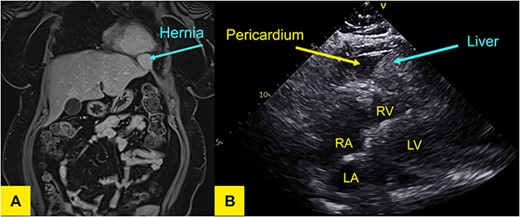

Laparoscopy was performed that revealed herniation of Segment 2 of the liver through a defect at the site of previous window formation (Fig. 2). Adhesiolysis of tissue attaching the liver to the diaphragm was performed and the plug of liver freed. There was no macroscopic evidence of vascular compromise to the herniated portion of liver.

Intraoperative photo of portion of Segment 2 of the liver herniating through defect in central tendon of diaphragm and into pericardial sac. Pericardial adhesions are connected to the capsule of liver.